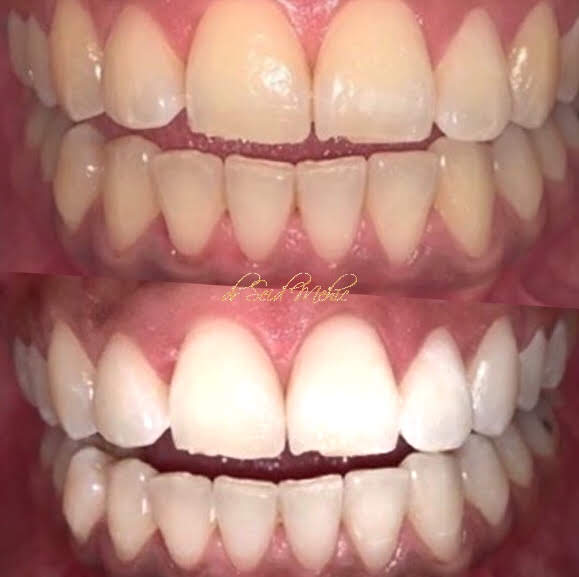

Izbjeljivanje zuba jedan je od najjednostavnijih, najbržih i najučinkovitijih načina kako

osvježiti i pomladiti svoj osmijeh. Stoga, izbjeljivanje zuba danas spada

među najtraženije stomatološke usluge.

Metode izbjeljivanja zuba su: lasersko i kućno izbjeljivanje zuba.

Laserom možete izbijeliti zube za 45 minuta u samo jednoj posjeti. Najbolji svjetski protokoli sigurnosti jamče zdravlje

desni i zuba u toku ali I nakon tretmana.

Kućno izbjeljivanje zuba podrazumijeva aplikaciju udlaga sa specijalnim gelom za izbjeljivanje, svakodnevno preko noći.